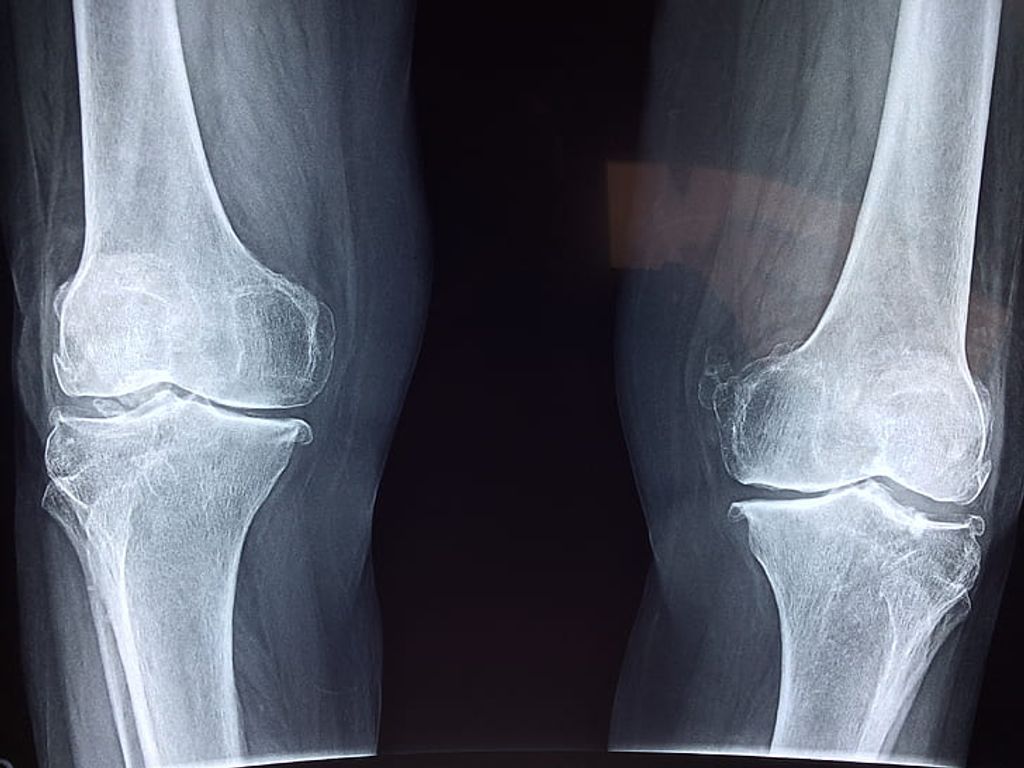

After recognizing the symptoms of osteoarthritis knee pain, we proceed to its diagnosis, which is crucial for tailoring the most effective management strategies. We begin with a thorough medical history and a physical examination. The presence of joint stiffness, swelling, and pain during movement can be indicative of osteoarthritis. To confirm the diagnosis, imaging tests such as X-rays or MRI scans are often employed. These tests reveal the extent of joint damage, including loss of cartilage and changes in bone structure.

Imaging Tests for Osteoarthritis Knee Pain:

• X-rays: Show bone spurs and cartilage loss

• MRI: Provides detailed images of soft tissues

After observing the symptoms of knee osteoarthritis, we proceed to its diagnosis, which is crucial for determining the appropriate treatment plan. We begin with a thorough medical history and a physical examination, focusing on the knee’s range of motion, stability, and strength. Radiographic tests, such as X-rays, are essential as they reveal the extent of joint damage and the presence of bone spurs.

To further assess the condition, we may also employ magnetic resonance imaging (MRI) to visualize soft tissue structures, including cartilage, ligaments, and the meniscus. However, an MRI is not always necessary for diagnosis, as the clinical presentation and X-rays often suffice.